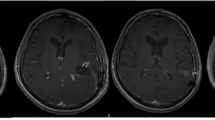

We recently investigated both prophylactic (pre-treatment) hyperbaric oxygen (HBO) strategy and HBOT (post-treatment) for treatment of repetitive mild traumatic brain injury (rmTBI) (personal communication: Drs. Lei Huang and Andre Obenaus). Repetitive mTBI is an important public health concern for sports athletes and active military personnel as subsequent injuries are thought to exacerbate existing neuropathology. Mild controlled cortical impact (CCI) was used to model rmTBI in adult rats. In rmTBI animals, a second mild CCI was delivered at the same location at 3 or 7 days after the initial impact. HBO pre-treatment or HBOT was given 1 hr daily at 2 ATA for 3 consecutive days either prior to or 24 hrs after the initial TBI, respectively. T2 weighted imaging (T2WI) and susceptibility weighted imaging (SWI) were acquired non-invasively from which lesion and hemorrhage volumes were quantified. Our results clearly demonstrated that both HBO pre-treatment and HBOT improved neuroimaging outcomes following rmTBI, in contrast to those seen in tissues without HBO intervention. There were significant reductions in the T2WI-derived lesion and SWI-identified hemorrhage volumes at 24 hrs after rmTBI (Figures 1, 2). The most dramatic neuroprotective effects were observed in animals receiving rmTBI 3 days apart where a 3-fold reduction in hemorrhage volumes was observed compared to Shams (Figure 2). Given that the pathophysiological processes underlying rmTBI likely involves cellular metabolic perturbations in the injured brain [32], a neuroprotective approach, namely, HBO pre-treatment or HBOT favoring cerebral aerobic metabolism could be beneficial. Similar findings have been reported in HBOT for human severe TBI [14].

Figure 1

HBO reduces rmTBI lesion volumes. Pre- and post-treatment with HBO reduces lesion volume identified from magnetic resonance imaging (MRI, T2 weighted images). Repetitive mild traumatic brain injury (rmTBI) was induced 3 days apart and resulted in ipsilateral tissue damage. On T2WI, hypointensities (white arrow) are consistent with bleeding while hyperintensities (black arrow) suggest edema formation. At 24 hrs after the rmTBI, HBO pre- or post-treatment significantly reduced the lesion size compared to untreated animals. The neuroprotective effects persisted to 14 days after the initial mTBI.